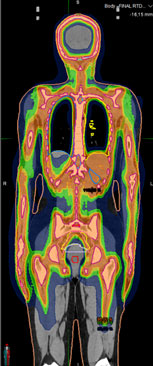

Пример дозового распределения при проведении таргетного тотального облучения костного мозга и лимфатической системы. |